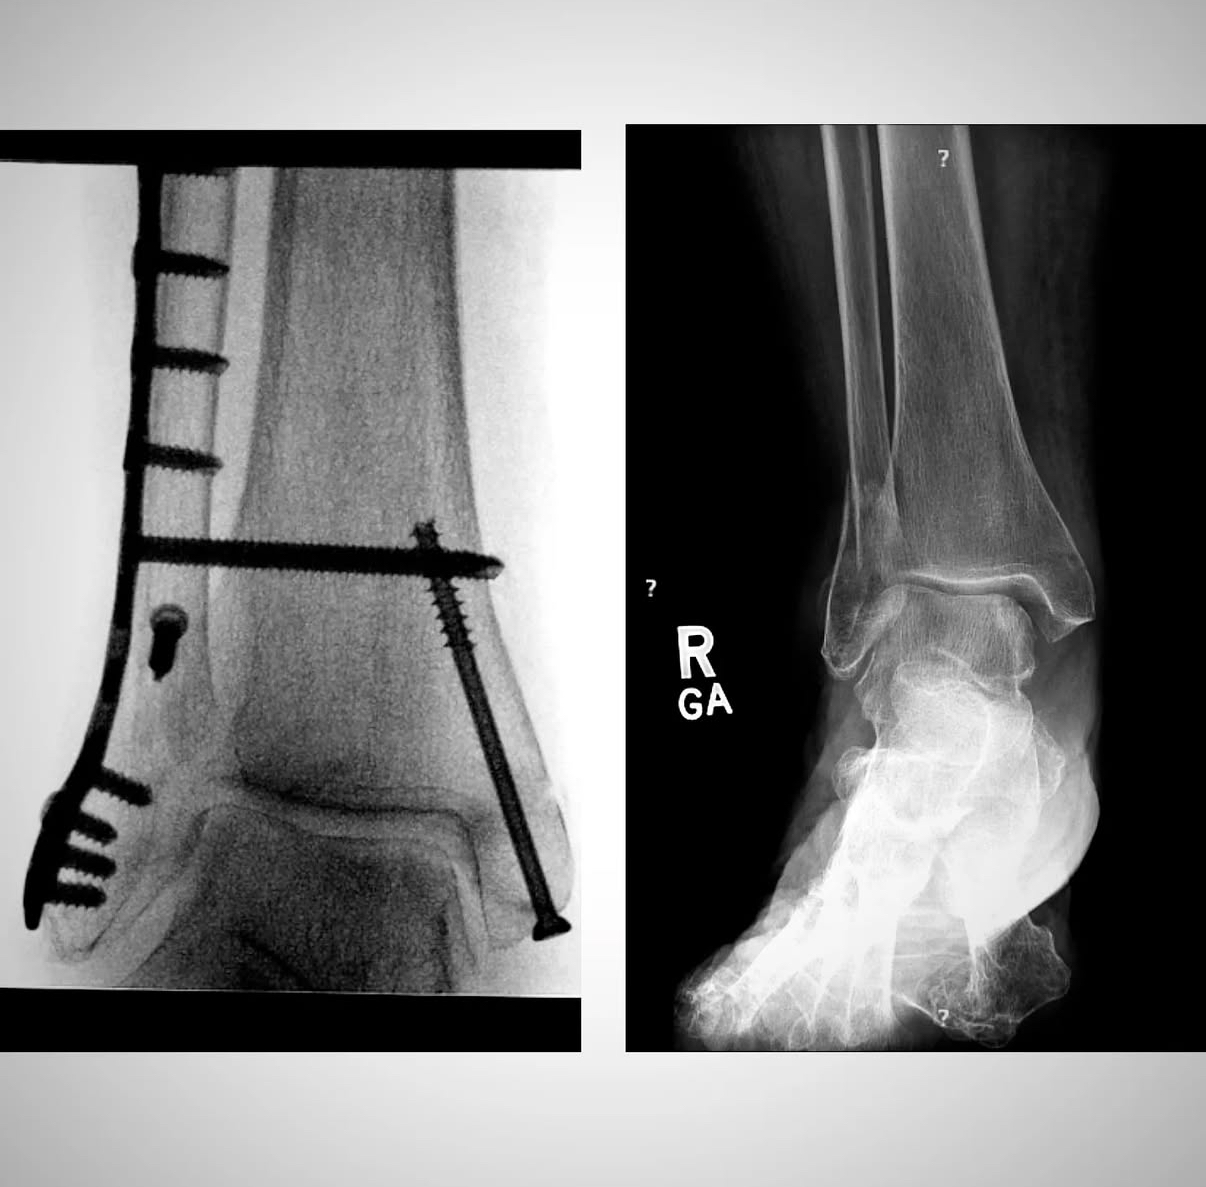

Ankle fracture repair

Pre-op XR Images

Postop XR Images